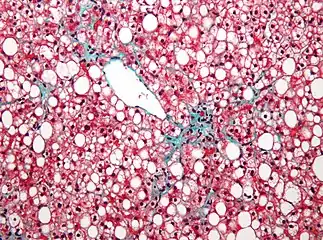

- Fatty liver disease (hepatic steatosis) is a reversible condition where large vacuoles of triglyceride fat accumulate in liver cells.[8] Non-alcoholic fatty liver disease is a spectrum of disease associated with obesity and metabolic syndrome.[9]

- Cirrhosis is the formation of fibrous tissue (fibrosis) in the place of liver cells that have died due to a variety of causes, including viral hepatitis, alcohol overconsumption, and other forms of liver toxicity. Cirrhosis causes chronic liver failure.[15]

Diffuse cirrhosis